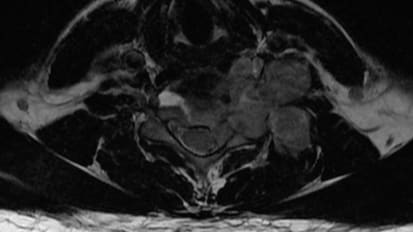

Johns Hopkins neurosurgeon Daniel Lubelski discusses the importance of pathology, biomarkers and genetics in treatment of spine tumors. Immunotherapy and targeted therapies are used to approach tumors that have been bio-banked and gene-sequenced, resulting in a tailored treatment plan. This, combined with advanced medical and surgical options, is leading to the best possible outcomes for patients with spine tumors.